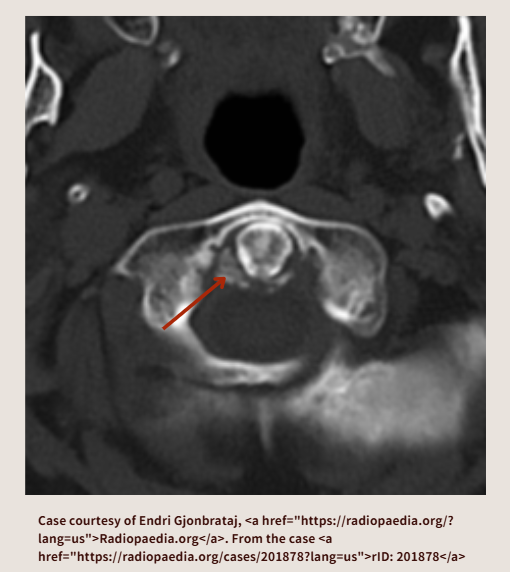

下のCT画像では、横靭帯(Transverse ligament)に石灰化が見られます。(赤矢印は自分で追加)